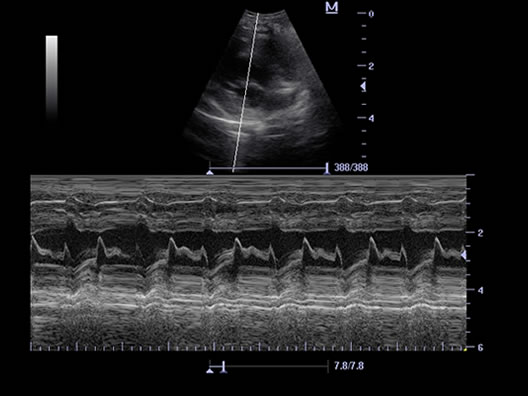

Free Xros M™

Auto measurement of anterior and posterior wall thickness providing accurate carotid status.